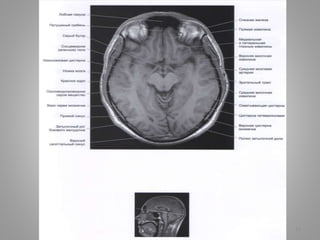

Великі цистерни головного мозку

• Велика (мозочково-мозкова) цистерна (cisterna magna, c. cerebellomedullaris) –

• Цистерна моста (препонтинна) - розташовується наперед від моста мозку, містить

базилярну артерію. Зєднується позаду з мосто-мозочково-мозковою цистерною та

субарахноідальним простором спинного мозку, попереду – з міжніжковою

цистрною.

• Базальна цистерна (c. suprasellar) має п'ятикутну форму, включає міжніжкову

цистерну (між ніжками мозку) і цистерну перехреста (між перехрестом зорових

нервів і лобними частками).

• Чотиригорбкова цистерна (вени Галена) (c. quadrigeminalis) розташовується між

мозолистим тілом і мозочком; у її ділянці можуть розташовуватись

субарахноідальні кисти

• Обвідна (охоплююча; по Синельникову - обхідна) цистерна (c. ambient) - канал

неправильної форми, що проходить по бокам ніжок мозку і даху середнього

мозку; сполучається з мостовою і міжніжковою цистернами спереду і

чотирегорбиковою цистерною ззаду.

• Цистерна бічної ямки великого мозку (cisterna fossae lateralis cerebri) -

розташовується в латеральній борозні великого мозку.

9